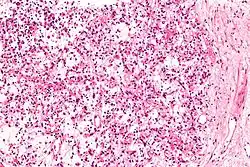

| Micrograph of an inflammatory myofibroblastic tumour of the kidney. Kidney biopsy. H&E stain. | |

Histopathologic examination of the tumors in IMT generally reveals myofibroblastic spindle cell sheets in a myxoid background (i.e. a background matrix containing gelatinous mucopolysaccharides and non-sulfated glycosaminoglycans); the matrix also contains inflammatory cells, particularly plasma cells and lymphocytes occasionally mixed with eosinophils and neutrophils. The epithelioid inflammatory myofibroblastic sarcoma subtype of IMT shows sheets of epithelioid to round cells within a myxoid (i.e. appears blue or purple compared to the normal red appearance of connective tissue when appropriately H&E stained and examined under the microscope), collagenous, or mixed myxoid-collagenous matrix, <5% spindle cells, and an inflammatory cell infiltrate that in most cases consists predominantly of neutrophils or, less often, small lymphocytes or eosinophils; plasma cells occur in only a minority of EIMS cases. The neoplastic cells in the tumors of 50% to 60% of IMT cases[2] and 100% of EIMS cases[3] express an ALK fusion protein. Other genetic abnormalities occur in these cells. Testing for the presence of the ALK fusion protein and other genetic abnormalities (see next section) can help diagnose IMT.[31]